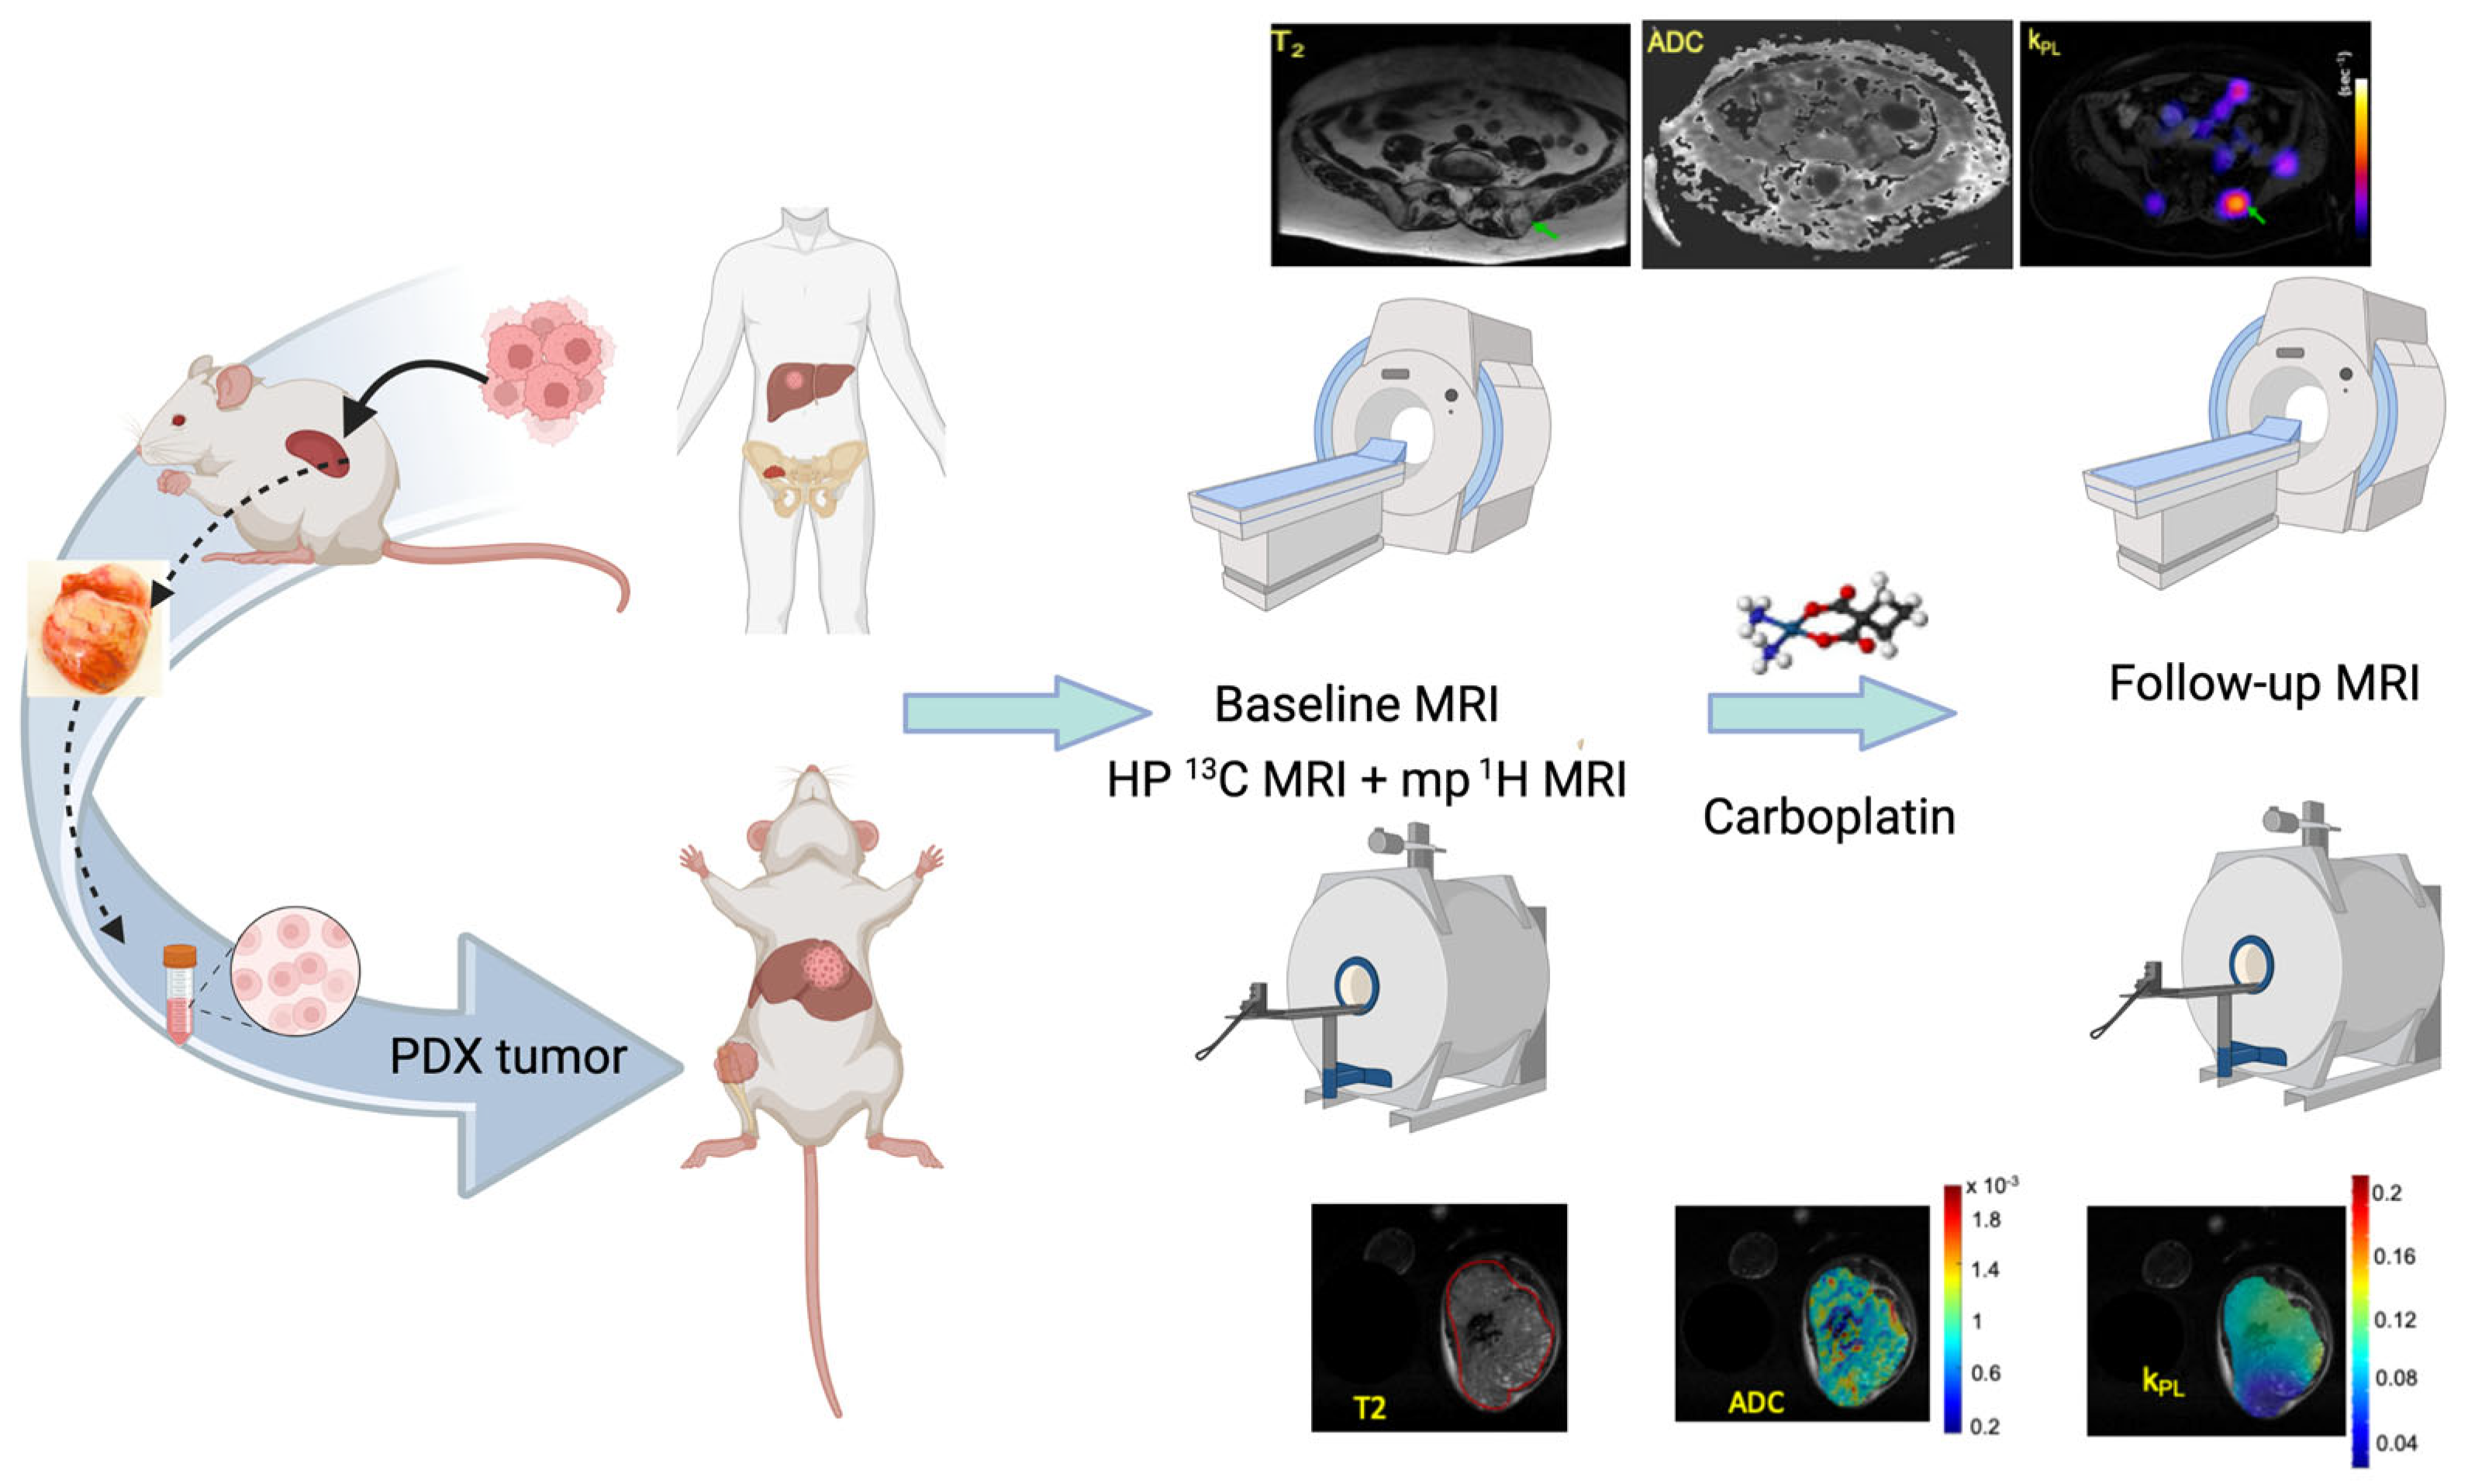

2.1. The UCSF Co-Clinical Quantitative Imaging of Small Cell Neuroendocrine Prostate Cancer Using Hyperpolarized 13C MRI